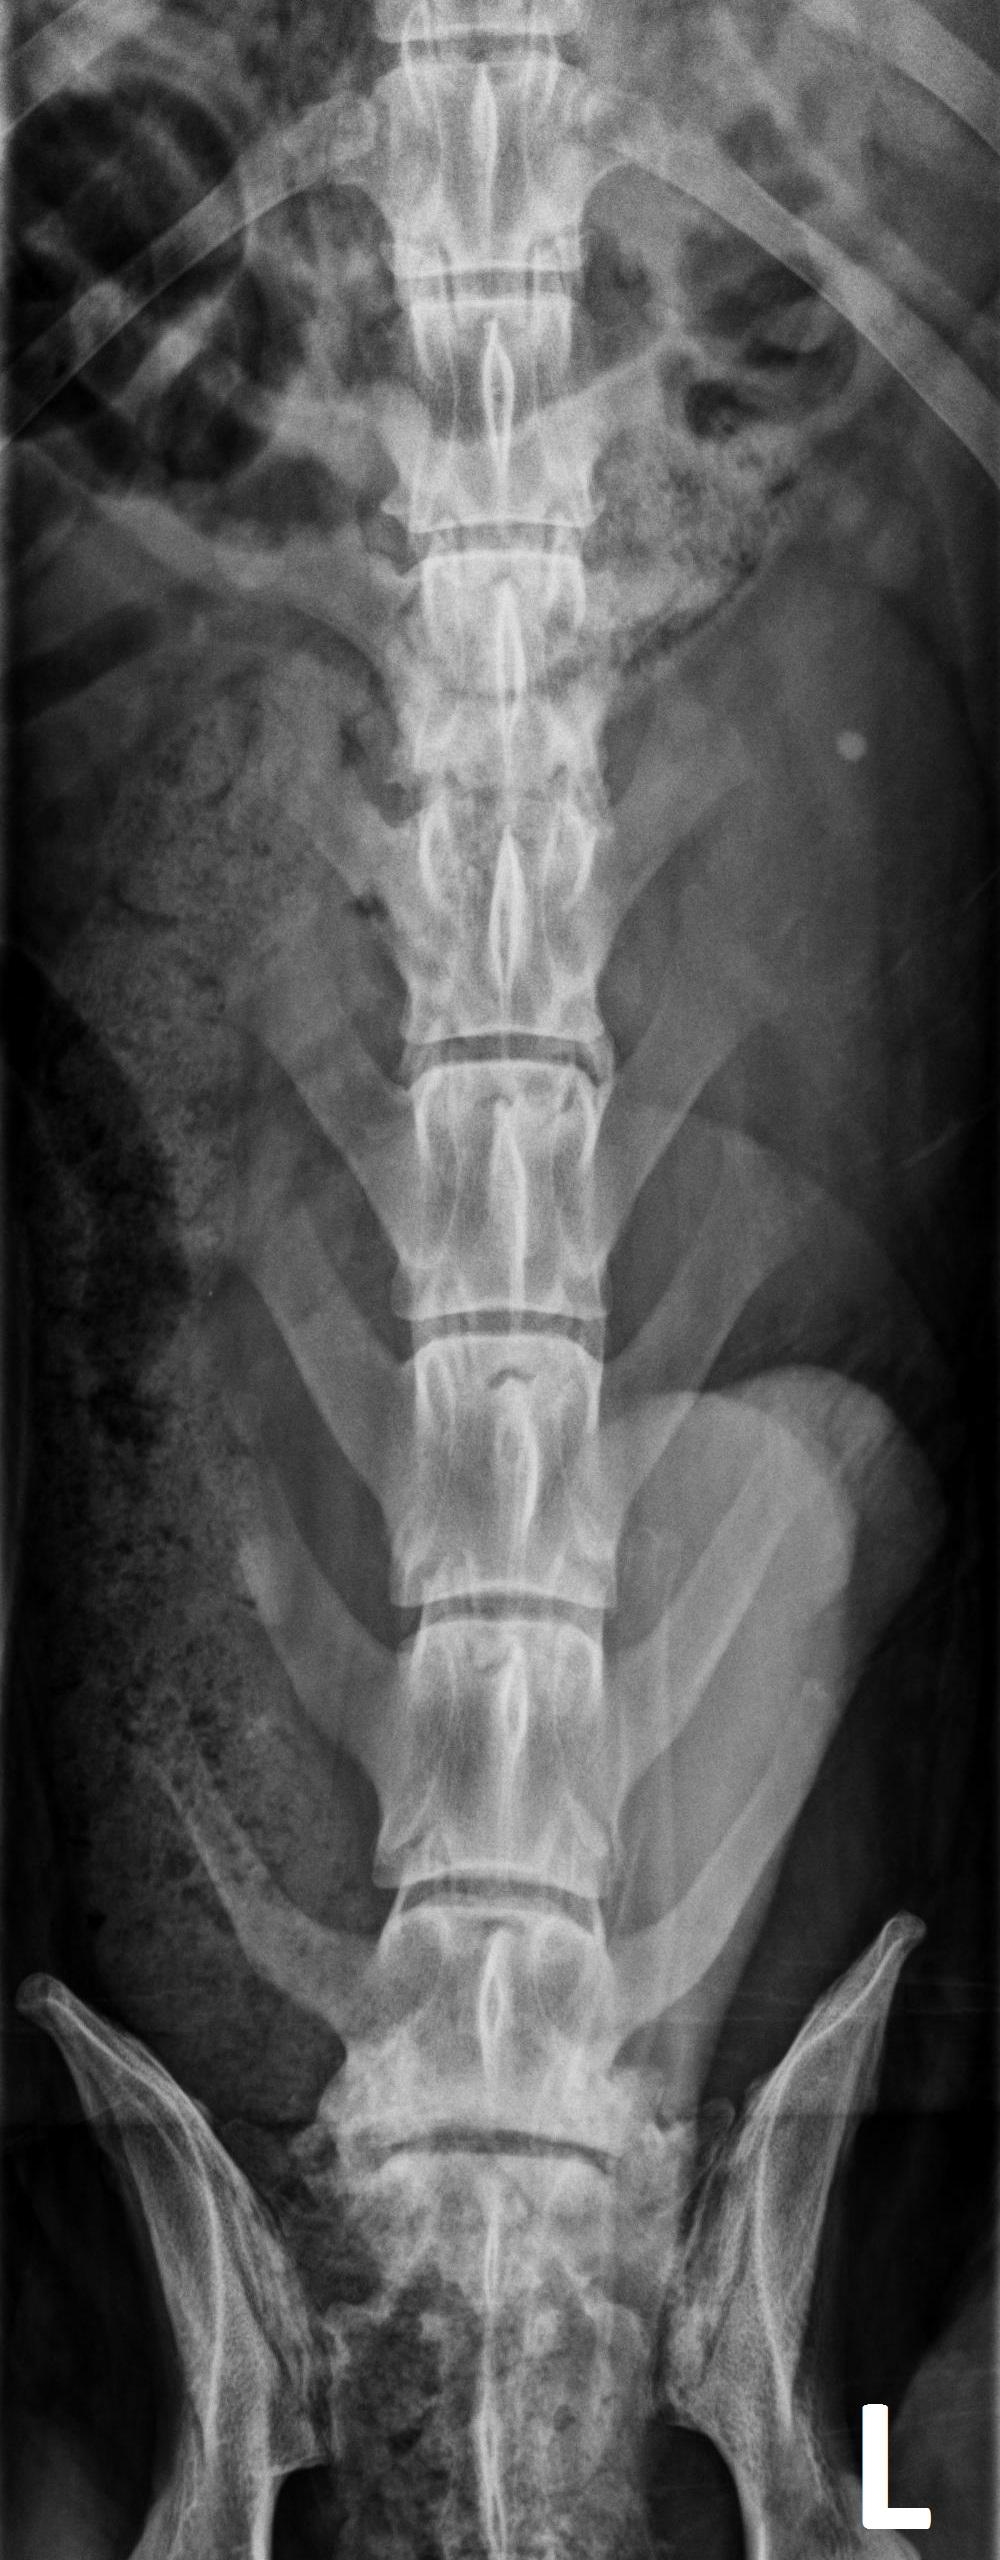

Orthogonale opnamen van de lumbale wervelkolom zijn beschikbaar voor interpretatie.

Er is een uitgesproken onregelmatigheid van de caudale eindplaat van L2 en de craniale eindplaat van L3, met vernauwing van de tussenwervelschijf L2-L3 en matige spondylosis deformans op dit niveau.

Er is multifocale verbreding van de lumbale facetgewrichten met onregelmatige peri-articulaire botnieuwvorming.

Er is vernauwing van de tussenwervelschijf L7-S1 met sclerose van de aangrenzende eindplaten en spondylosis deformans op dit niveau.

Lichte spondylosis deformans wordt opgemerkt ter hoogte van bijkomende lumbale tussenwervelschijven.

Een goed afgelijnde, ronde, mineraal-dense structuur wordt waargenomen in de linker nier.